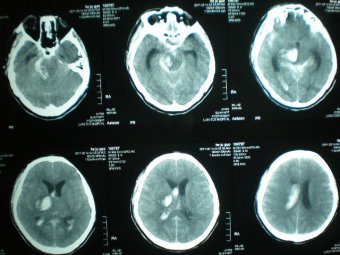

腦出血微創(chuàng)治療技術(shù) 日期:2015-12-29 10:34:00 點(diǎn)擊:1657 好評:29

2007年濰坊市市立醫(yī)院派急診科主任、副主任醫(yī)師劉樹森到北京301醫(yī)院進(jìn)修腦出血微創(chuàng)術(shù)。北京301醫(yī)院腦出血微創(chuàng)術(shù)技術(shù)居全國先進(jìn)水平。經(jīng)過半年進(jìn)修,劉樹森熟練掌握了腦出血微創(chuàng)治療術(shù)。2008年開始應(yīng)用北京301腦...